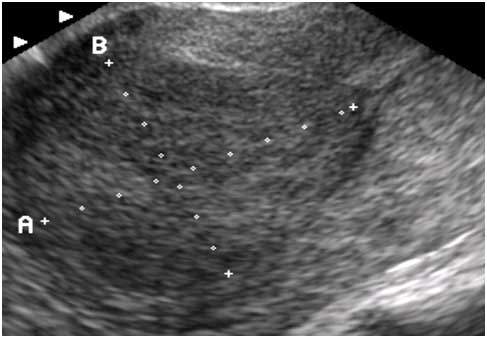

자궁 근종을 초음파로 보았을 때는 가로, 세로, 부피의 형태가 가늠할 수 있다.(아래 사진 좌) 이에 반해 선근증은 자궁 내막에 생겨 자궁벽 내로 침투하기 때문에 자궁 근종에 비해 근종 근처에 혈관들이 많이 밀집되어 있다. 그래서 선근종을 검사할 때는 초음파로 정확한 형태를 파악하기 힘들다고 한다. 일반적으로는 막대기처럼 길쭉하게 뻗어있는 모습을 보인다. 산부인과에서 선근증을 진단할 때는 먼저 초음파로 혈관들이 많은지 여부를 먼저 살펴보고 MRI나 조직 검사로 구체적인 상태를 검사한다고 한다.

선근종 초음파 예시.jpg